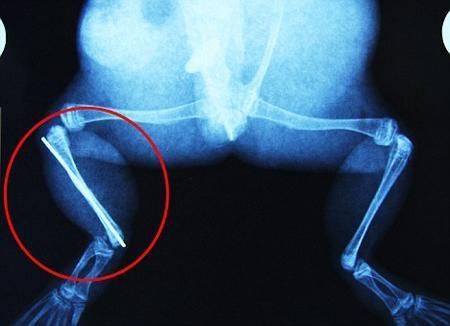

布魯萊的主人,居住在南非約翰內(nèi)斯堡附近的62歲的安妮·米恩斯說:“我對(duì)這只青蛙如此關(guān)心,人們一定認(rèn)為我瘋了,但是我無法眼睜睜看著它那么痛苦。青蛙因其靈活的腿腳而著稱,一想到布魯萊的腿里要留下一個(gè)薄金屬片,我就感到心痛。然而我知道,如果不進(jìn)行手術(shù),布魯萊以后就沒辦法動(dòng)彈了。因此我匆匆趕到獸醫(yī)那里,央求他給這只可憐的青蛙動(dòng)手術(shù)。這位獸醫(yī)整天救助小貓小狗,他很難理解為什么我這么擔(dān)心一只青蛙,但是最終他還是答應(yīng)了給布魯萊做手術(shù)。手術(shù)后是幾個(gè)小時(shí)的焦急等待,我們希望它能快快蘇醒過來。不過現(xiàn)在它的傷口已經(jīng)愈合,又能在花園里跳來跳去了。X光照射顯示,它會(huì)恢復(fù)的跟以前一樣!

野生生物專家安妮經(jīng)常為學(xué)校寫教材,她認(rèn)為這是人類第一次通過手術(shù)給一只青蛙接斷腿。在手術(shù)開始階段,獸醫(yī)把少量給狗用的麻醉藥注入到這只青蛙體內(nèi),讓它失去知覺。然后他在布魯萊的斷腿上切開一個(gè)小口,把一根小鋼針植入腿里。最后獸醫(yī)給它縫了9針,把切口縫合在一起。僅僅幾周后,布魯萊就能在安妮家附近活動(dòng)了。這只青蛙大約已有25歲,主要以嚙齒動(dòng)物、蛇和其他青蛙為食。布魯萊所屬的牛蛙種群正在不斷減小,目前只能在非洲南部的濕地里才能看到這種青蛙。

安妮有2個(gè)孩子,她已經(jīng)從事20多年兩棲動(dòng)物保護(hù)工作。她認(rèn)為鄰居家的狗狗在把布魯萊從地下刨出來的時(shí)候,它正在地下冬眠、她說:“世界上只有這個(gè)地區(qū)能看到這種牛蛙,這種青蛙現(xiàn)在變得越來越稀少。因?yàn)槲覐氖乱吧锉Wo(hù)工作,因此認(rèn)識(shí)很多兩棲動(dòng)物專家,但是以前他們誰也沒見過這種事情?吹讲剪斎R越來越健康我非常開心,F(xiàn)在還需要一段時(shí)間,它的金屬腿和它的骨骼才能融為一體,那時(shí)布魯萊會(huì)跟以前一樣健康。我們認(rèn)為這個(gè)過程需要幾周時(shí)間,但是一旦它完全康復(fù),我希望把它放歸大自然,讓它重新回到它最鐘愛的濕地里。”